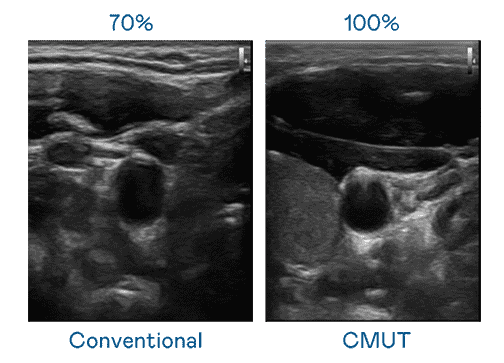

CMUT 技术是一种用电容式微机电元件来产生超音波讯号的技术。。。与传统 PZT 压电式技术相比,,,CMUT 频宽增加 30%,,,更宽频的超音波讯号让影像解析度大幅提升,,是实现高影像品质医疗超音波扫描、、、促进精准医疗发展的关键技术。。

大频宽带来超清晰影像

超音波影像的解析度高低,,,,首先取决于探头能发出的讯号频宽。。。。2468BET CMUT 可提供高清晰的超音波讯号,,,提供高频宽、、高灵敏度、、影像纹理细节更高的超音波影像,,协助医护人员缩短影像判读时间及利用精准的医疗影像进行诊断。。